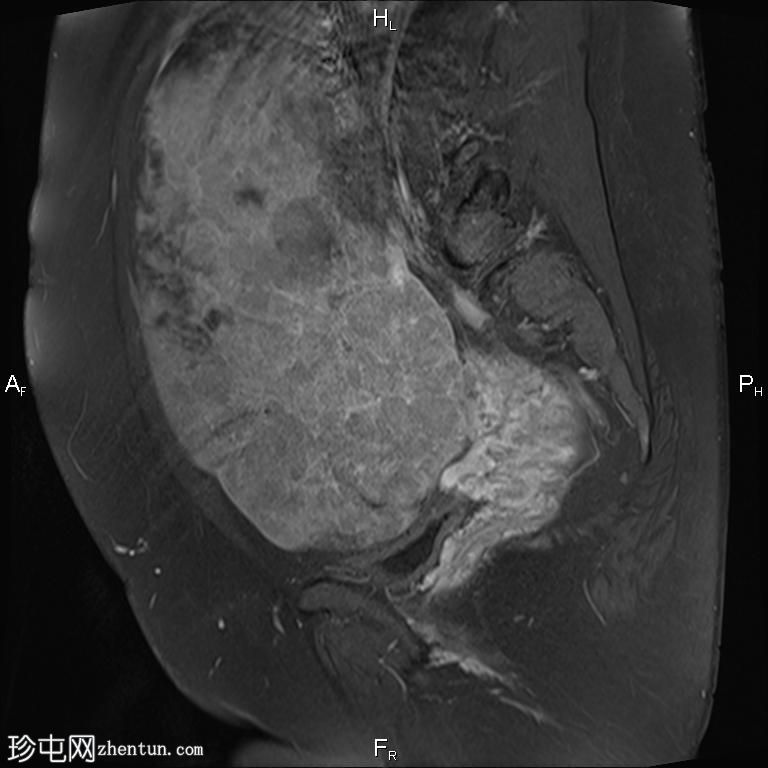

矢状位

T2

盆腔内可见一巨大多分叶实性肿块,内部有隔膜,T2WI信号不均匀,T1WI信号不均匀,呈低信号。肿块内散在分布囊性/坏死性病变。

肿块外可见子宫和右侧卵巢,肿块似源自左侧卵巢。该肿块压迫膀胱和两侧远端输尿管,并导致肠管和血管结构移位,但无侵袭或包裹征象。

造影后,肿块呈不均匀强化,隔膜强化。

远端髂腹旁和两侧髂骨旁区域可见少量肿大淋巴结。